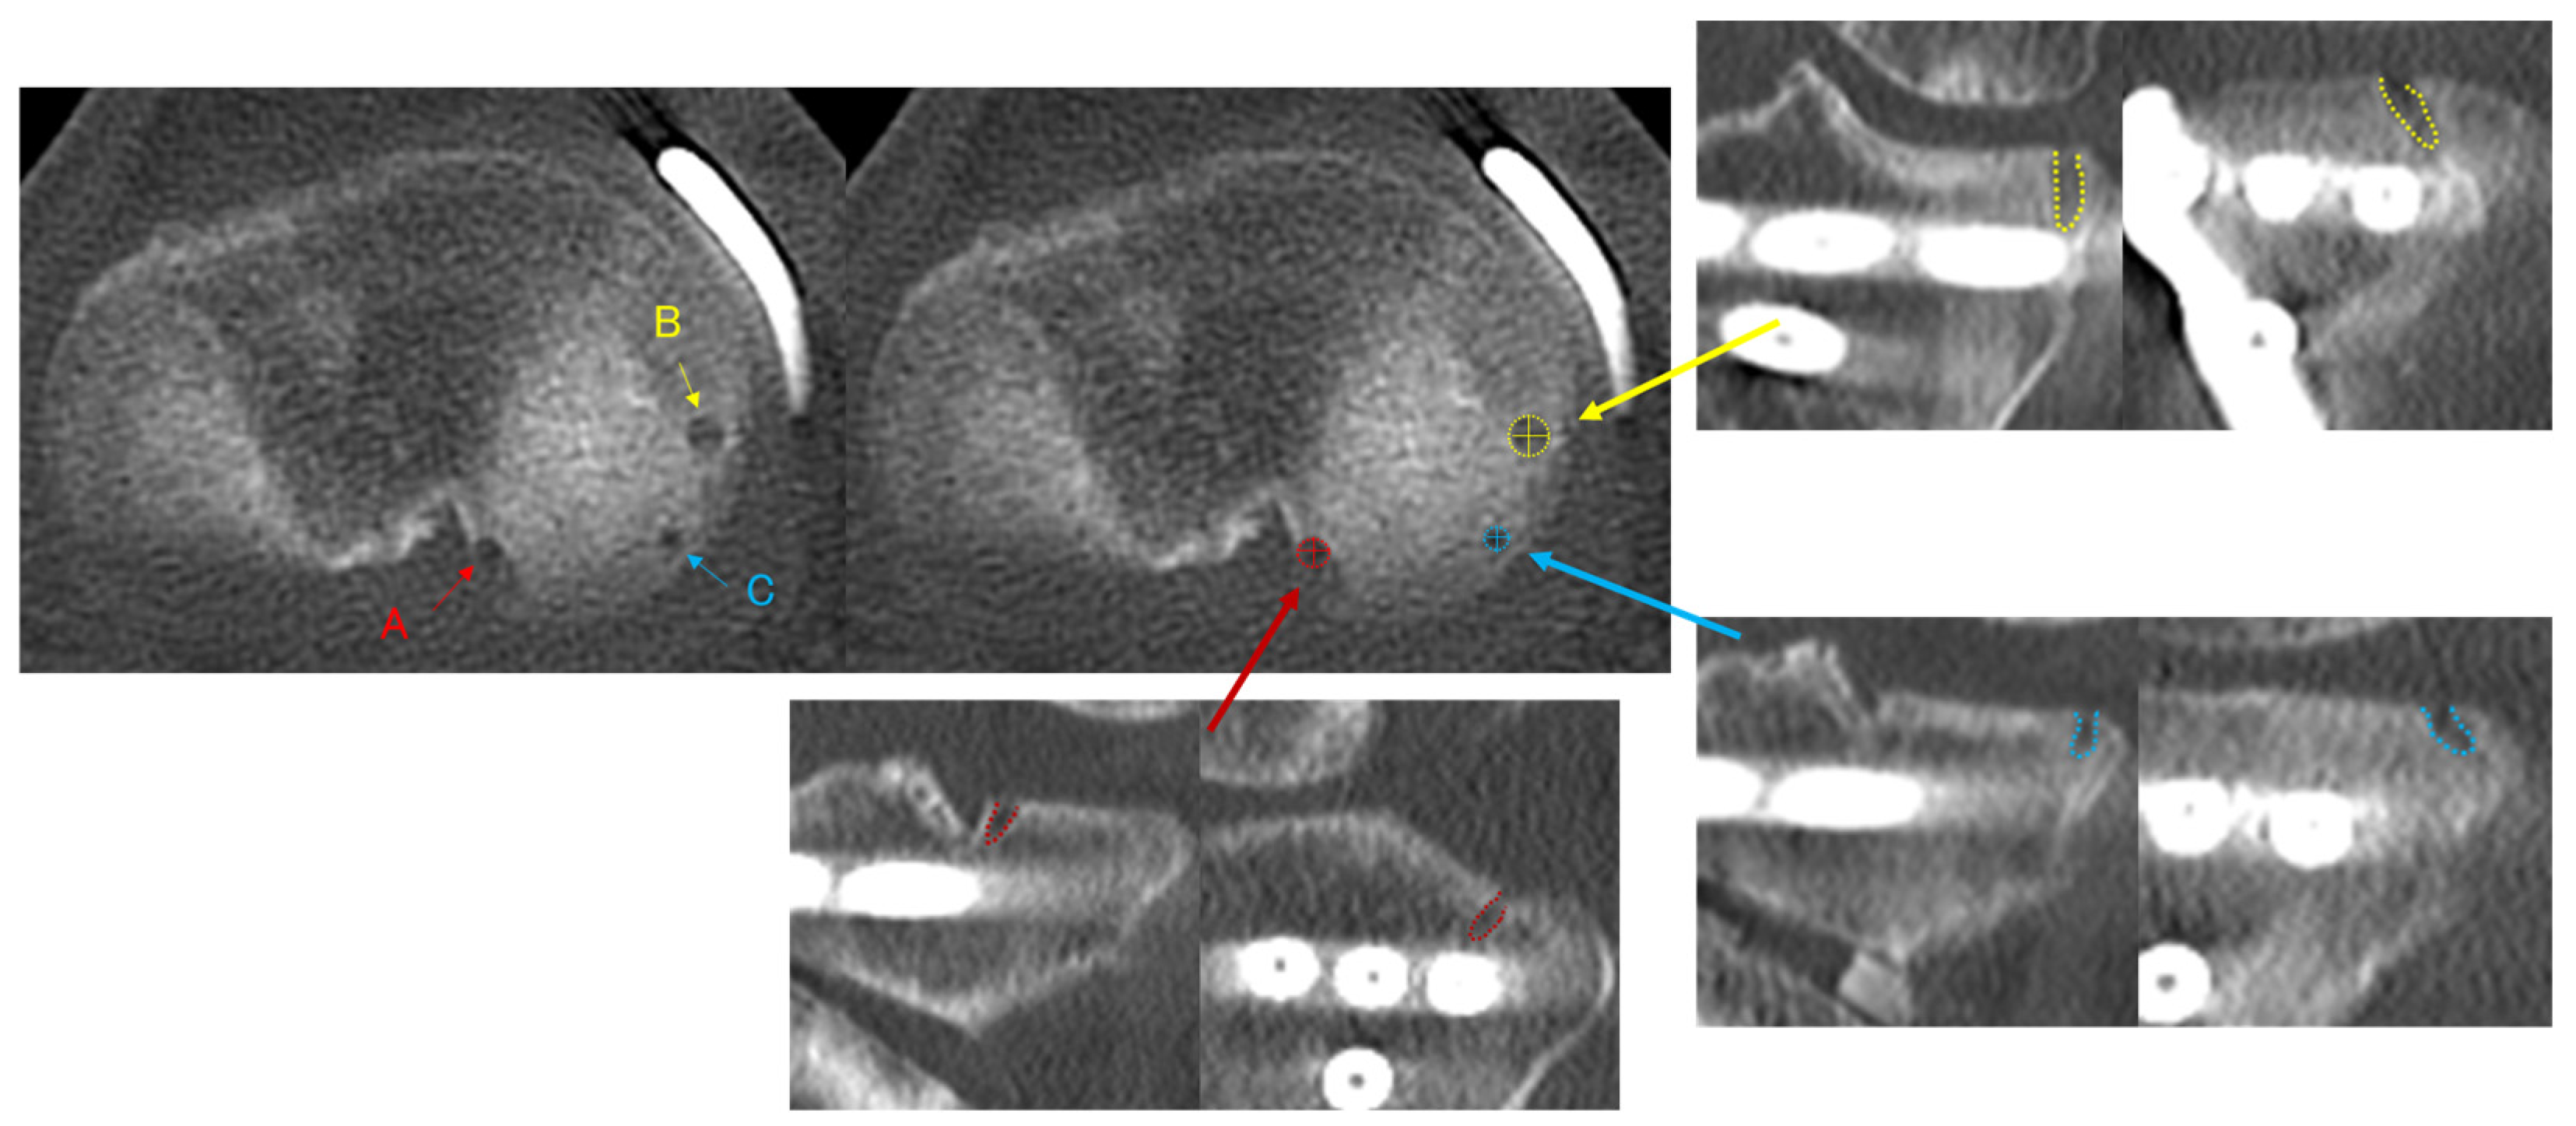

Figure 5. CT images showing anchor holes and anchor hole width (AHW) for each anchor: (A) the anchor hole for the anchor used in MMPRT repair (R-anchor), (B) the anchor hole for the midbody anchor (M-anchor) used in the centralization technique, and (C) the anchor hole for the midbody–posterior anchor (MP-anchor). The maximum anteroposterior and mediolateral AHW (AP-AHW and ML-AHW) were measured.

Multiplanar reconstructed computed tomography (MPR-CT) imaging (SCE-NARIA View; FUJIFILM, Tokyo, Japan) was performed at 1, 3, and 6 months, and at 1 year postoperatively. CT imaging was conducted not only to quantitatively evaluate time-dependent changes in anchor hole width (AHW) but also for the clinical assessment of bone healing after OWHTO. CT was considered essential because subtle morphological changes in AHW, as well as bone healing at the osteotomy site, cannot be reliably assessed using plain radiographs or magnetic resonance imaging due to insufficient spatial resolution. All CT examinations were performed using a predefined low-dose imaging protocol to minimize radiation exposure; the volume CT dose index (CTDIvol) for each scan was <5 mGy, which is substantially lower than that of standard diagnostic knee CT protocols. The repeated CT imaging protocol was justified by both research and clinical purposes and was approved by the institutional review board. The AHW was evaluated for the anchor used for MMPRT repair (root anchor; R-anchor), the centralization anchor placed from the midbody to the slightly posterior region of the meniscus (midbody anchor; M-anchor), and the anchor placed at the midbody–posterior transition zone (midbody–posterior anchor; MP-anchor) (Figure 5). The maximum anteroposterior and mediolateral AHW (AP-AHW and ML-AHW) were measured on MPR-CT images. The postoperative 1-month AHW was defined as the initial reference value (baseline), and subsequent changes in AHW at 3 months, 6 months, and 1 year postoperatively were evaluated relative to this baseline. The slice thickness of the MPR-CT images was 0.625 mm. Intraobserver reliability of the measurements was assessed using the ICC. For all 30 knees, the same observer performed repeated measurements of the AP-AHW and ML-AHW for each anchor after a 4-week interval. The intraobserver ICCs ranged from 0.91 to 0.92 for the R-anchor, 0.92 to 0.93 for the M-anchor, and 0.90 to 0.92 for the MP-anchor, indicating excellent reliability. Interobserver reliability was also evaluated using the ICC between two independent observers. The interobserver ICCs ranged from 0.88 to 0.90 for the R-anchor, 0.87 to 0.89 for the M-anchor, and 0.88 to 0.89 for the MP-anchor, likewise indicating excellent reliability.